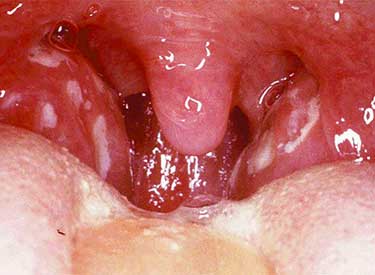

- мигдалини, м’яке піднебіння, дужки, задня стінка глотки стають яскраво-червоними, набряклими;

- поступово в горлі формуються бульбашки, слизова стає рихлою;

- бульбашки на мигдалинах, дужках, м’якому небі і в глотці або заповнені прозорим вмістом, або кров’яним, тому везикули мають вигляд червоних точок;

- нові пухирці утворюють невеликі ерозії, у ослаблених дітей або дорослих везикули можуть зливатися у великі виразки;

На поверхні слизової задньої стінки глотки на тлі запалення і почервоніння можна виявити дрібні бульбашки. Вони можуть покривати практично всю поверхню мигдалин. Якщо доторкнутися до них ложкою, оболонка швидко розривається і випливає кровянистое вміст.

Запалення глотки при герпесной ангіні зберігається протягом 6-7 днів. Через 5-6 днів бульбашки починають лопатися, і мигдалини покриваються численними ерозіями і виразками. При будь-якому дотику вони починають кровоточити.

- Яскраво-червоні виразки на небі я язичку.

- Невеликі бульбашки в ротовій порожнині з мутнуватою рідиною всередині.

- Збільшені, червоні мигдалини.

- Жовтуватий наліт на мигдалинах.

Крім запалення слизової ротоглотки, збільшуються мигдалики, їх поверхня червоніє, розпушується, з’являються характерні бульбашки з прозорим вмістом. Збільшуються підщелепні та привушні лімфатичні вузли. Шкірні покриви бліді, температура тіла підвищена.

На фото показано, як виглядає герпесвірусна ангіна у вигляді висипу, прозорих бульбашок, оточених щільним кільцем сполучної тканини. Гнійнички болючі при пальпації. Дозріваючи, починають лопатися, покриватися тканиною.